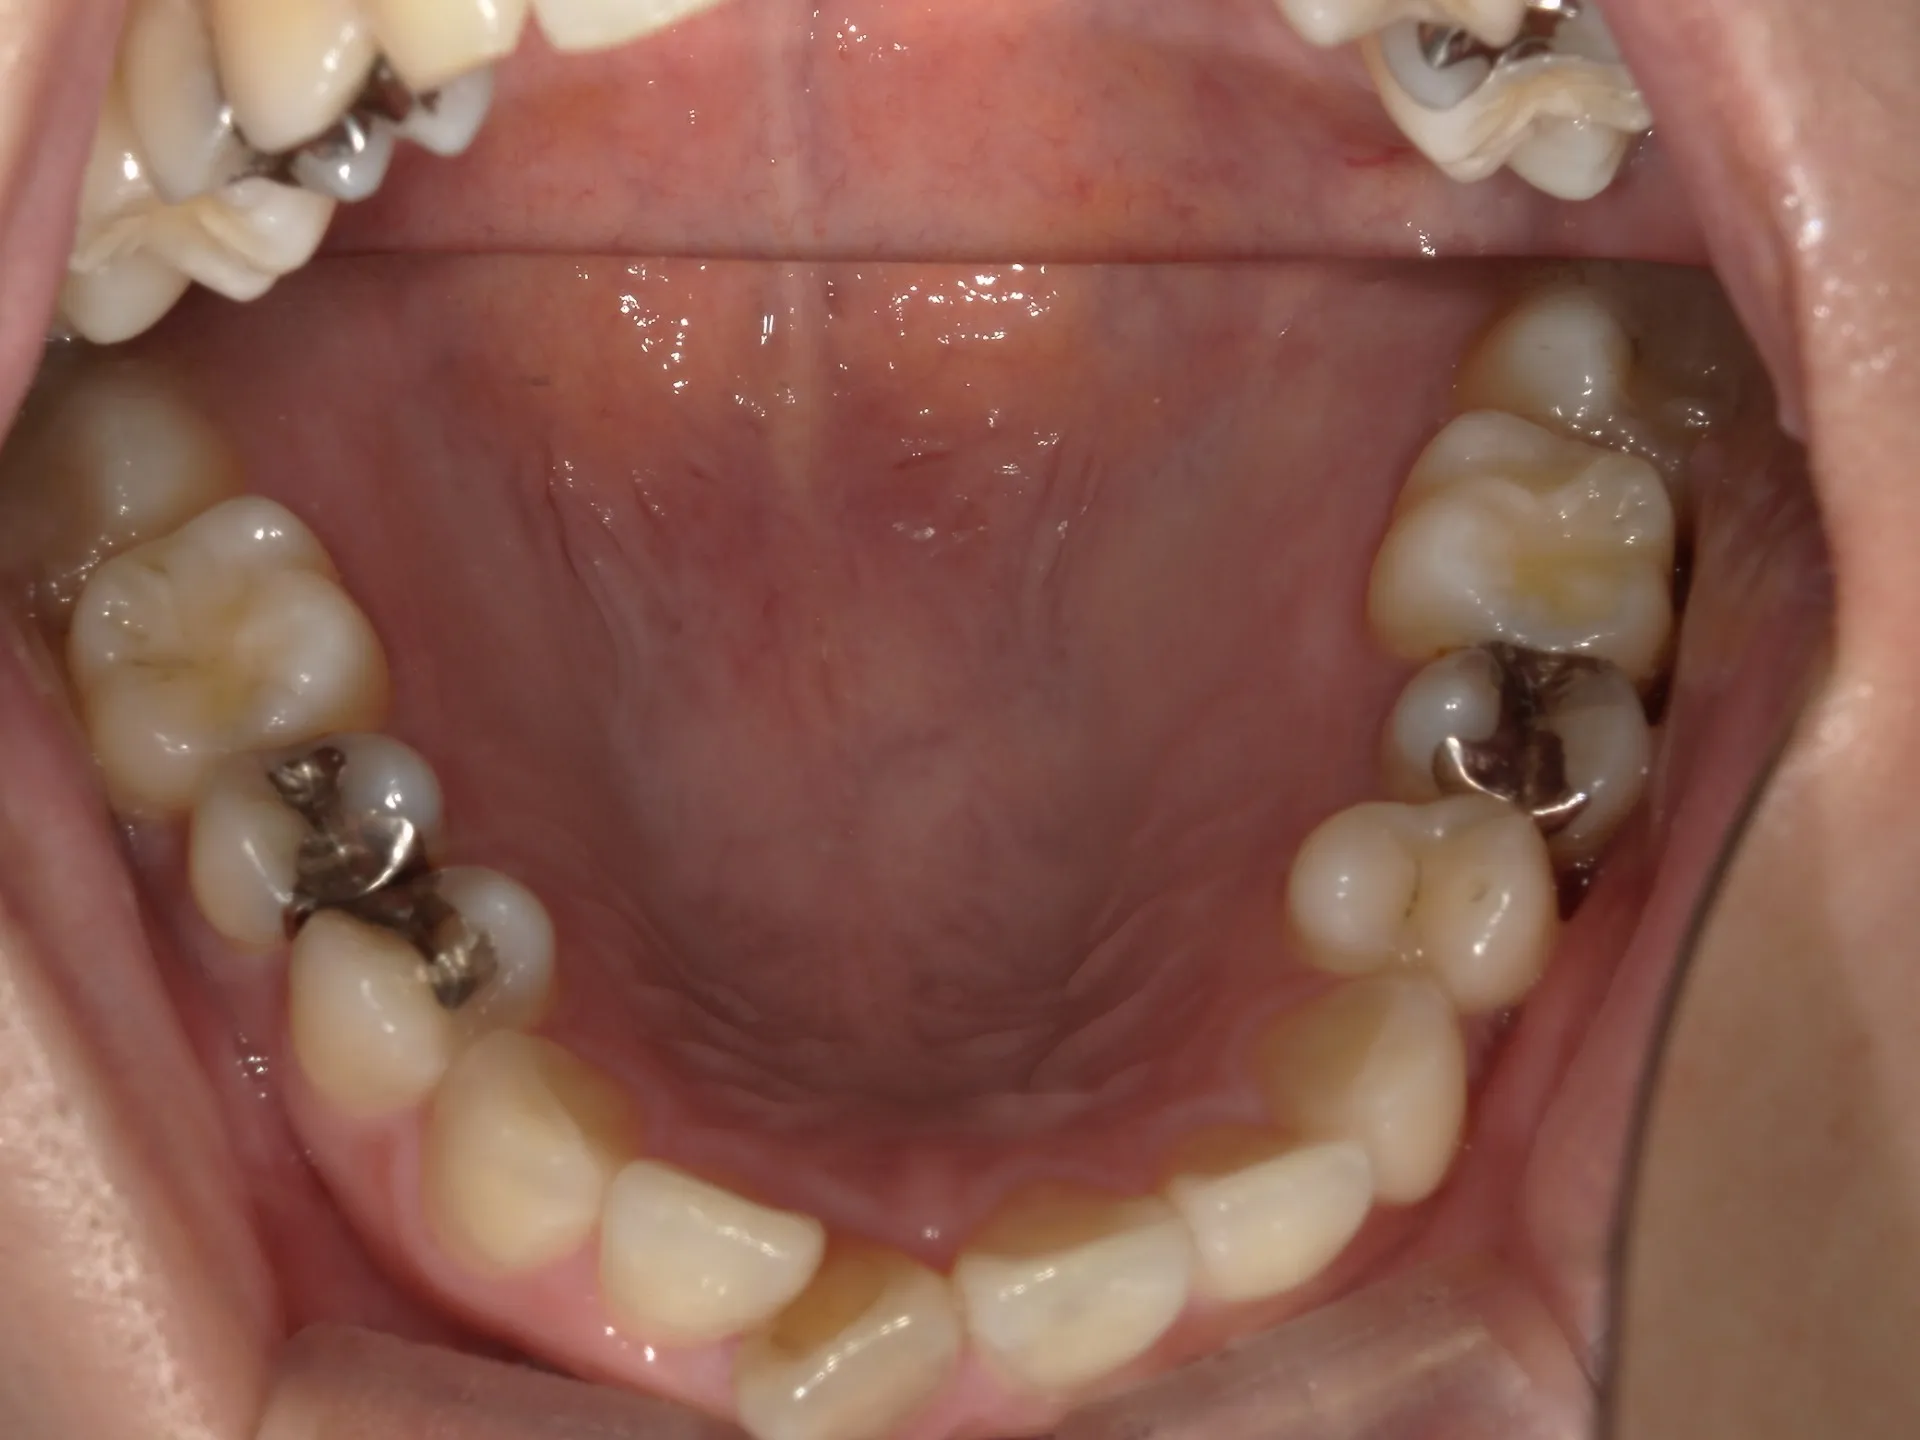

今回はねじれてしまった前歯の矯正治療をインビザラインというマウスピース矯正で治療した症例をご紹介いたします。